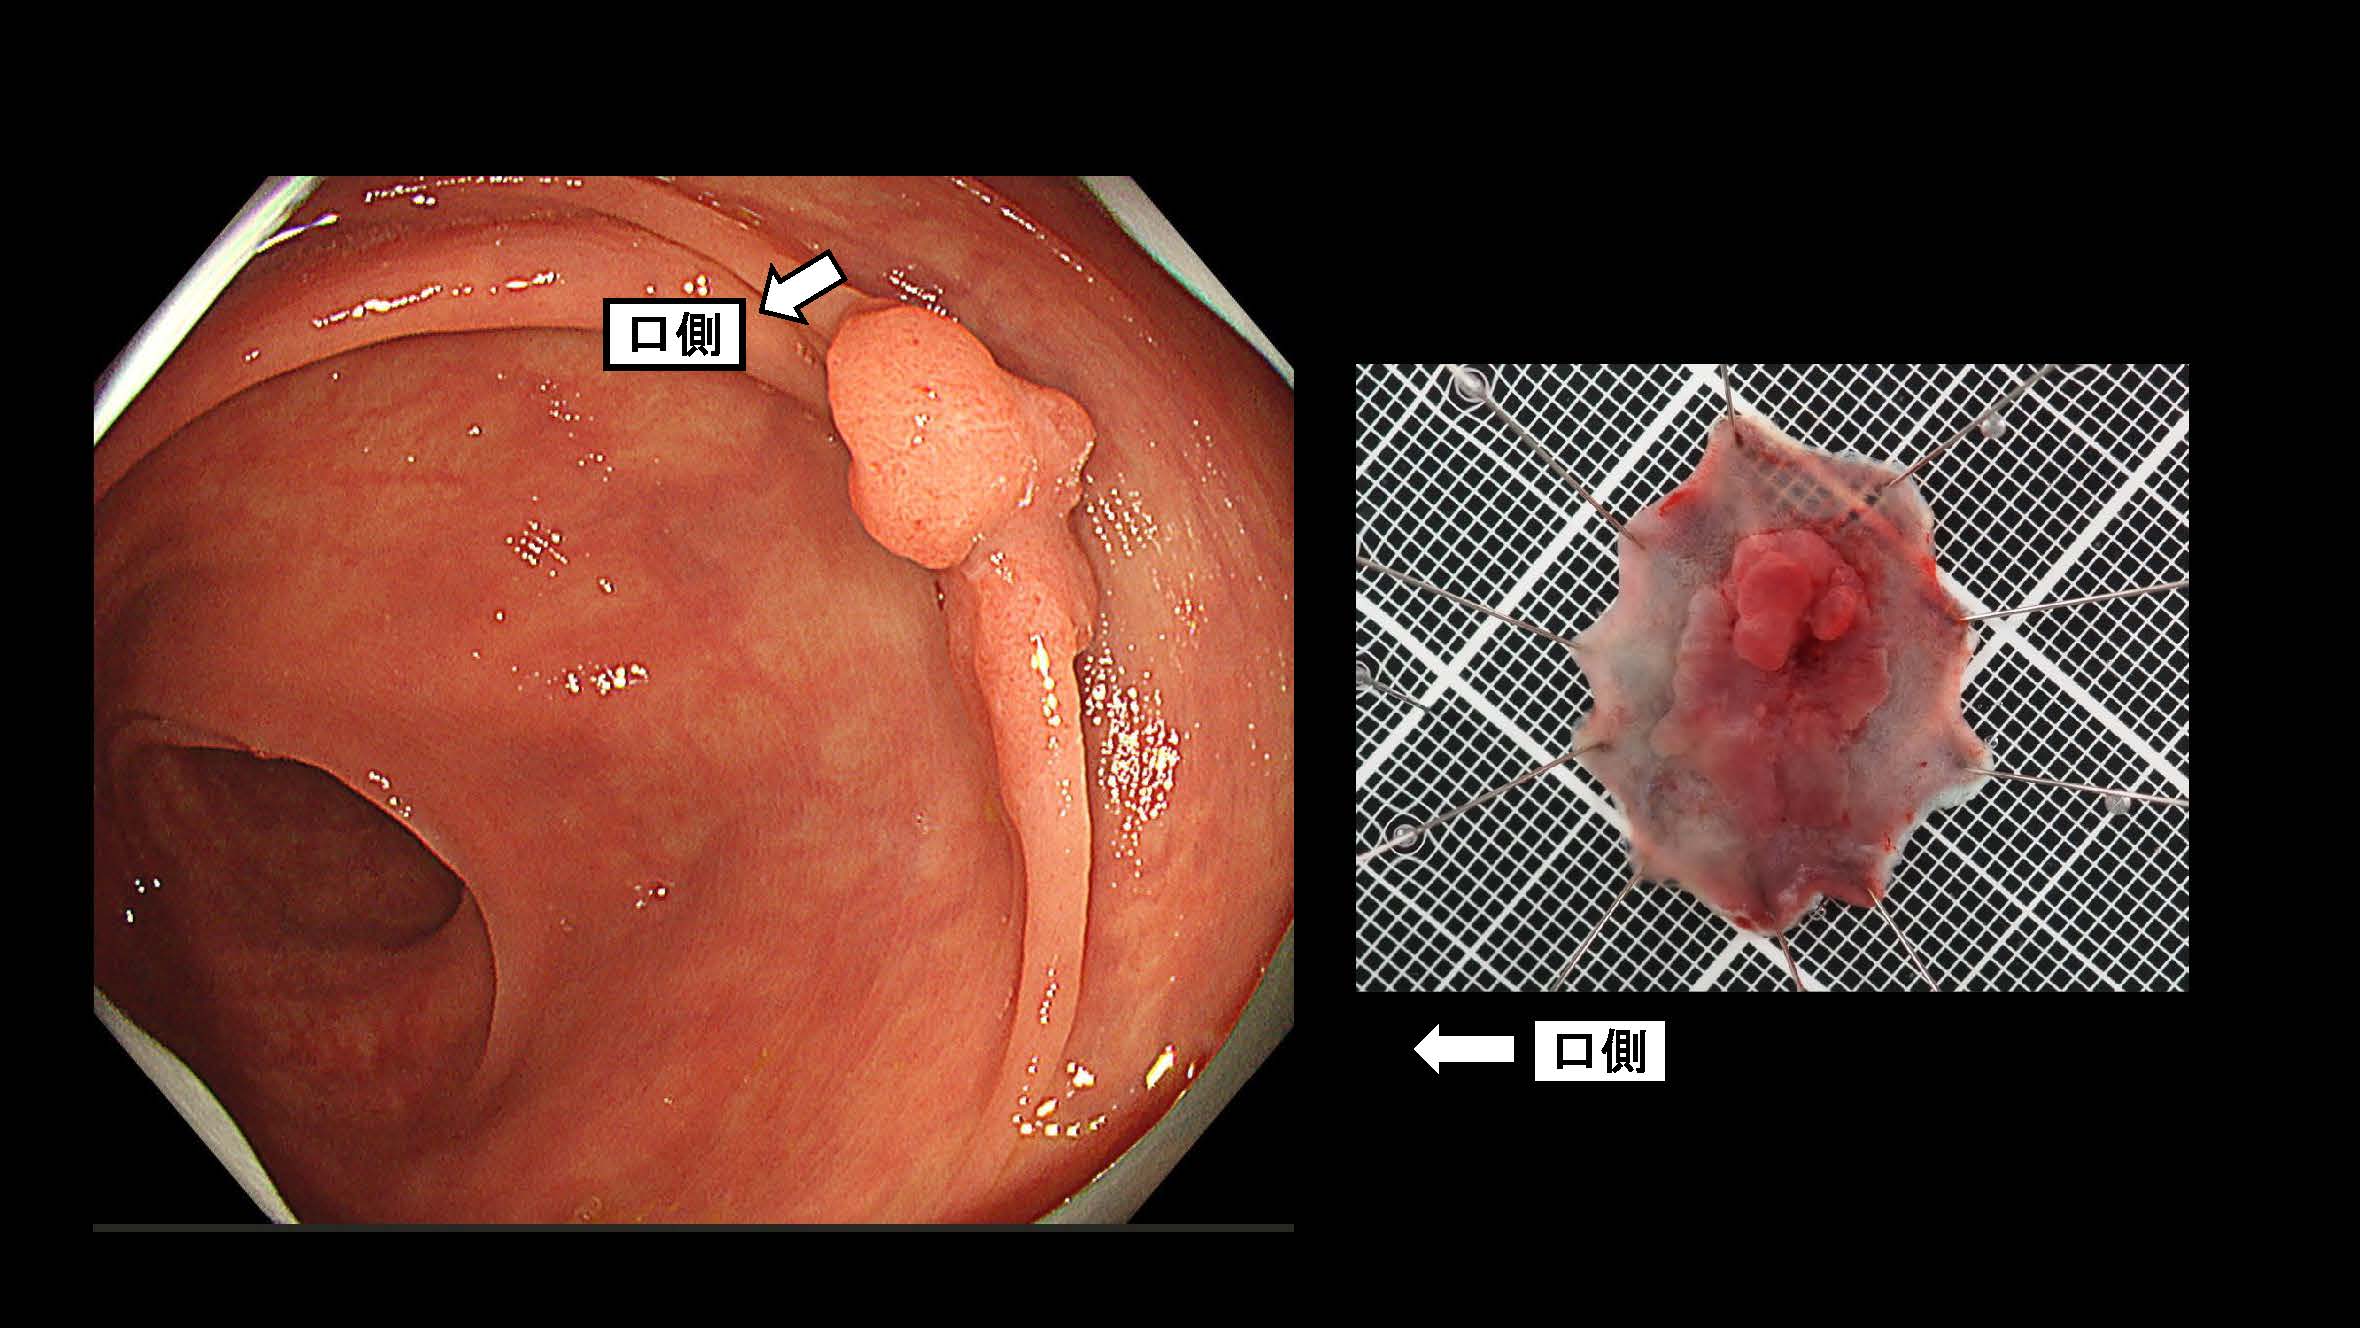

消化管Mapping~大腸~ 2025.6.11

消化管Mapping~大腸~

消化器内科

内視鏡検査・治療

消化管Mapping